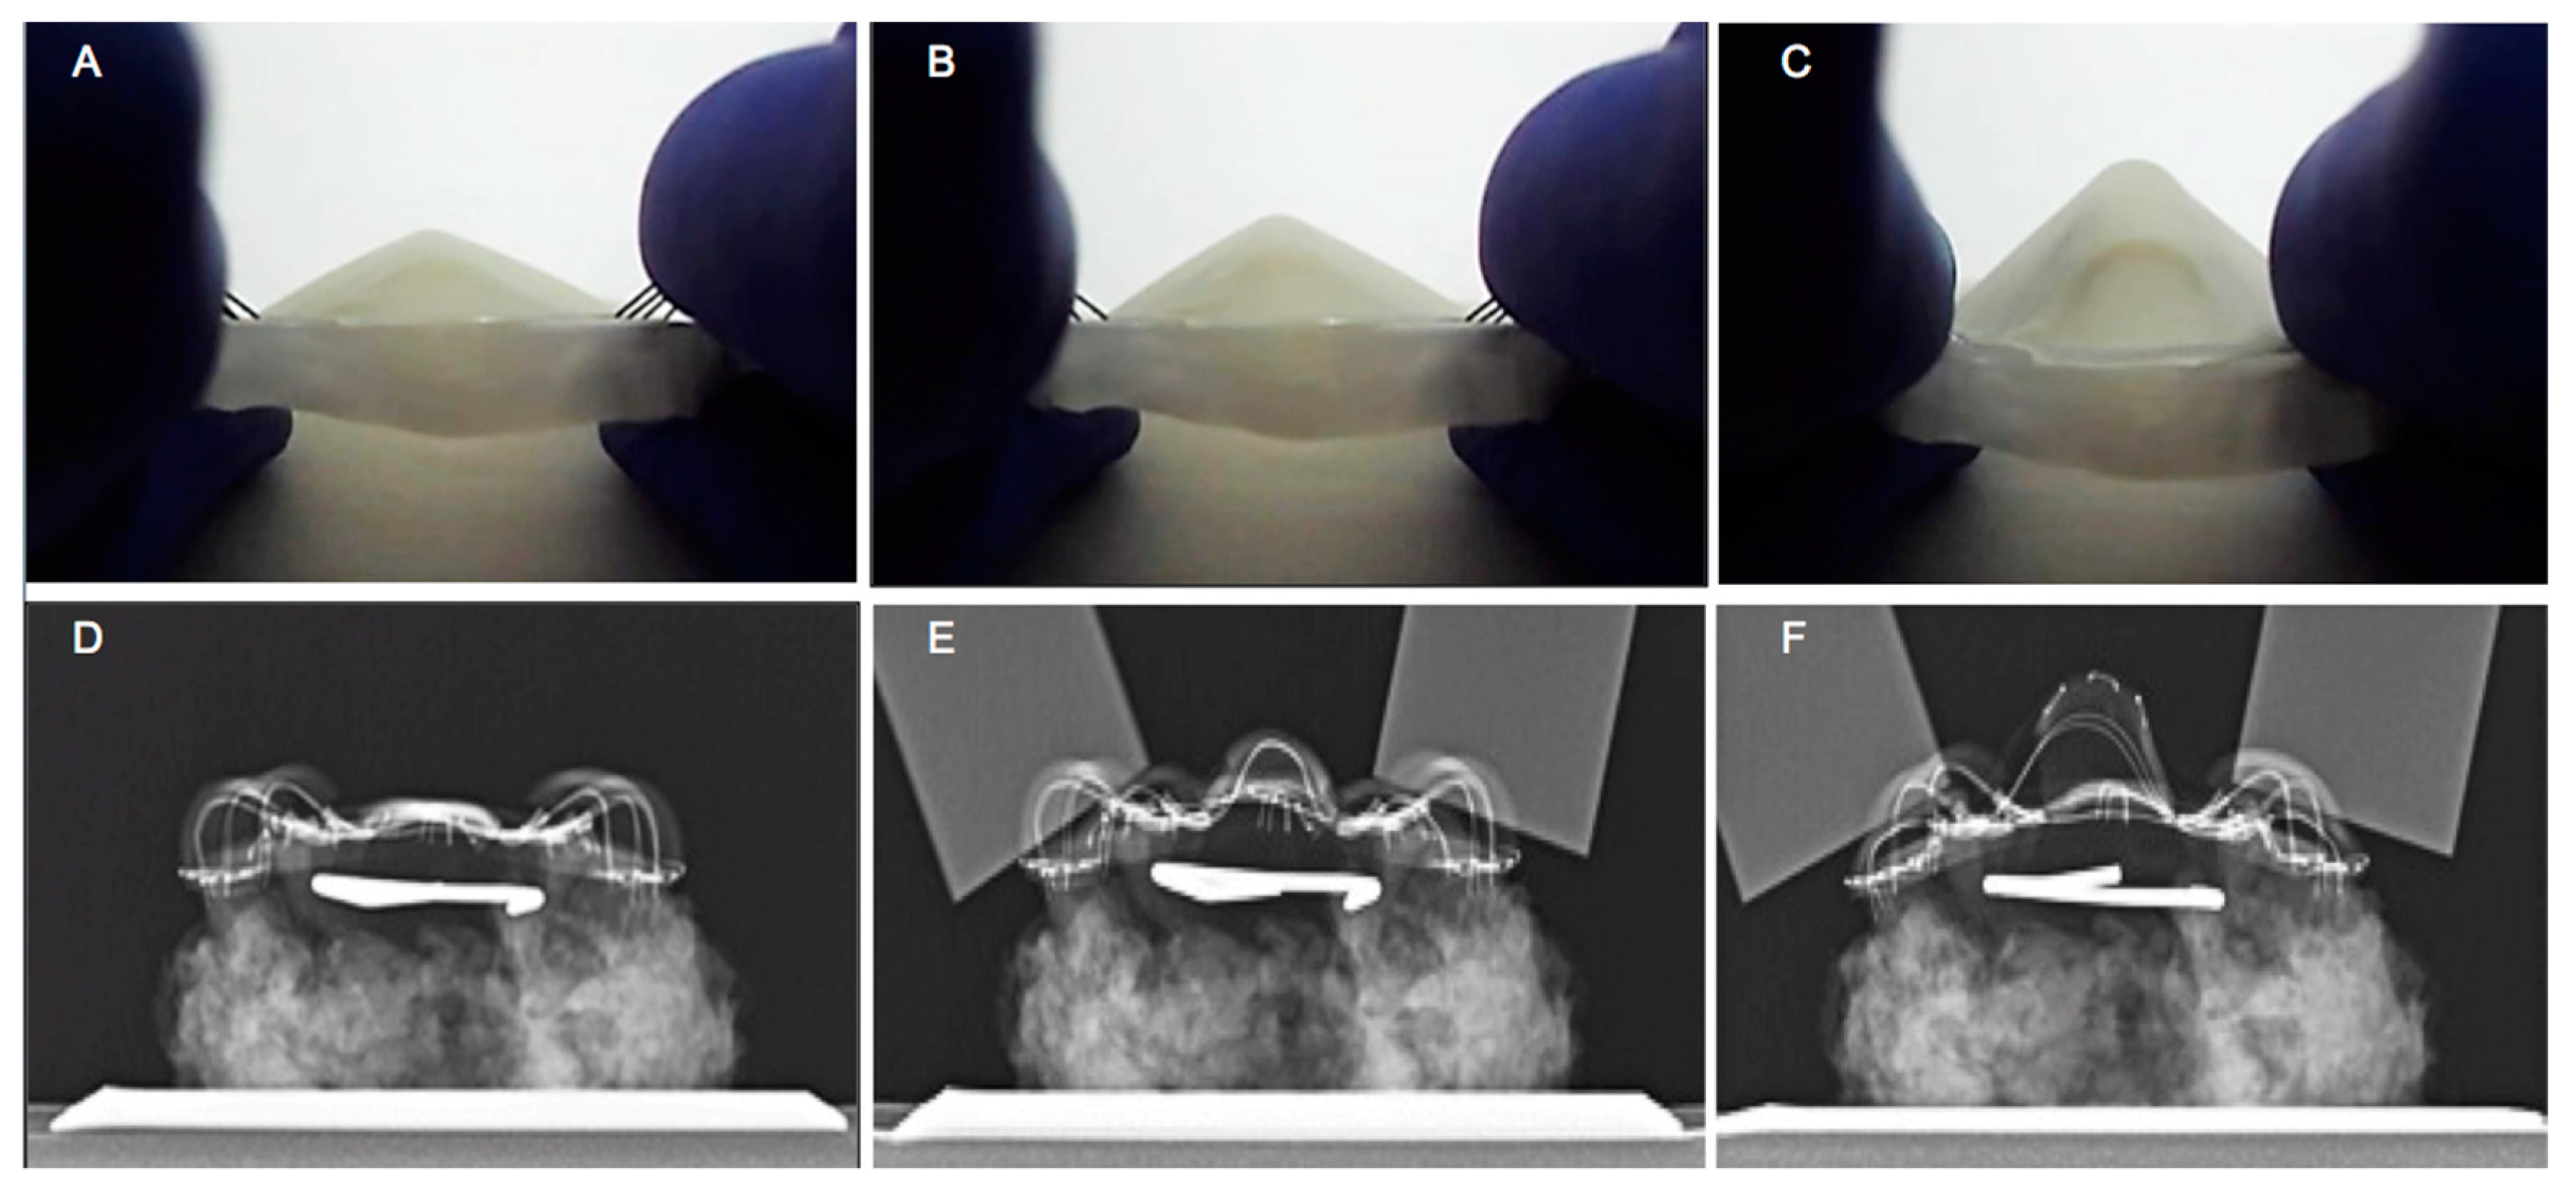

3.4. TPAD Performance Evaluation using Cadaveric Head Model